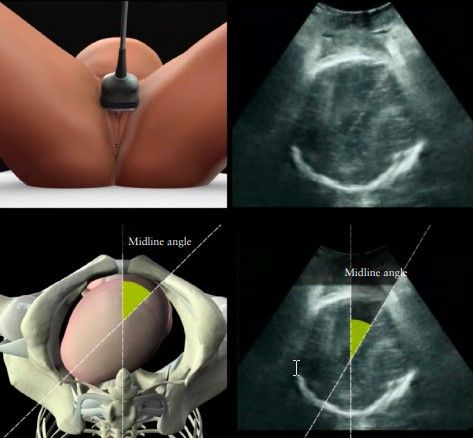

Messung head perineum distance (HDP) und midline angle durch Drehen der Sonde in die Horizontale (s. Bild unten). Es soll leichter Druck ausgeübt werden.

Head perineum distance

- Korreliert mit der noch zu bewältigenden Distanz im Geburtskanal

- Unter 4cm mit erfolgreichem VE assoziiert

- Bei Adipositas nicht verlässlich

Midline angle

- Evaluiert die Rotation des kindlichen Köpfchens

- Rotation ≥ 45◦ korreliert mit einem Höhenstand ≤ +2 cm (in 98.6%)

- Rotation < 45◦ korreliert mit einem Höhenstand ≥ +3 cm